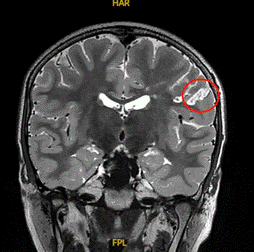

结节性硬化症(TSC):mTOR信号通路异常导致脑内多发结节,引发顽固性痉挛或局灶性癫痫,同时大部分患者存在基因异常,需要通过外科手段来治疗。

图为11岁女孩结节性硬化症,室管膜下巨细胞星形细胞瘤(上图)及右额皮层结节(下左、下右图),2期手术后癫痫无发作